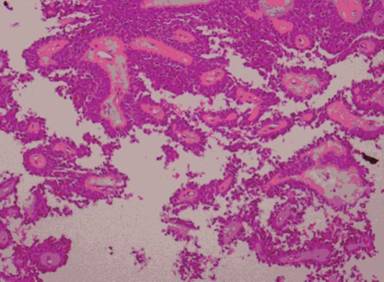

Histopathological examination of the resected tumor revealed that the tumor was composed of large areas of pseudopapillary structures with hyalinized fibrovascular cores lined by several layers of fragile epithelial cells with clear to eosinophilic cytoplasm, variable mucinous changes within the core with solid focal areas. Cells showed round/oval nuclei, finely stippled chromatin, nuclear grooves, indistinct nucleoli, few mitoses which was consistent with solid and cystic papillary neoplasm of the pancreas (Figure 3). No evidence of recurrence during a 2-year follow up period.

Figure 3. Low power shows polygonal cells with a pseudopapillary appearance (magnification: x10). |